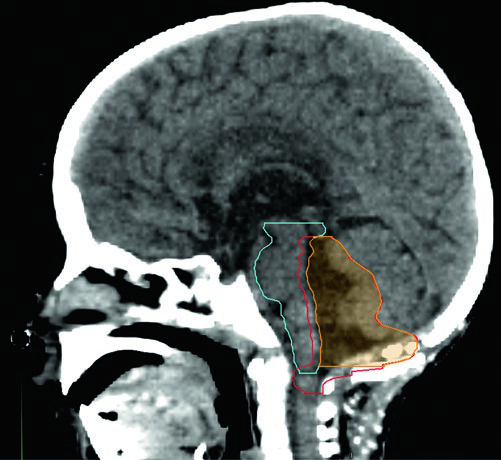

Volúmenes para boost de fosa posterior completa

| Volumen | Definición |

|---|---|

| GTV | Lecho tumoral con enfermedad residual, paredes de la cavidad y áreas señaladas por el neurocirujano. |

| CTVFP | Toda la fosa posterior incluyendo el tronco cerebral completo. Límites: base del cráneo anteriormente, tentorio superiormente, foramen magno inferiormente. El hueso del cráneo restringe posterior y lateralmente. |

| PTVFP | CTVFP + 3 a 5 mm según frecuencia de imagen y experiencia institucional. |

Fuente: Target Volume Delineation and Field Setup, 2nd Edition (Table 34.3)